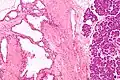

![]() Micrografía mostrando un cistoadenoma seroso del páncreas. H&E stain. | ||

El cistoadenoma seroso del páncreas es un tumor benigno de este órgano. Generalmente se encuentra en la cola del páncreas,[1] y puede estar asociado con el síndrome de von Hippel-Lindau.[2]

En contraste con algunos de los otros tumores del páncreas que forman quistes (como la neoplasia mucinosa papilar intraductal y la neoplasia quística mucinosa), las neoplasias quísticas serosas son casi siempre completamente benignas. Hay algunas excepciones; en raras ocasiones, se han descrito casos de cistoadenocarcinomas serosos malignos aislados.[3] Además, las neoplasias quísticas serosas crecen lentamente y, si crecen lo suficiente, pueden presionar los órganos adyacentes y causar síntomas.